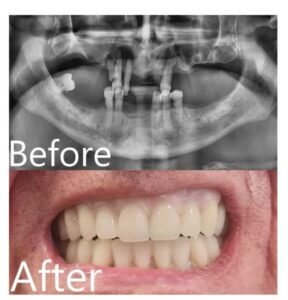

Our cases